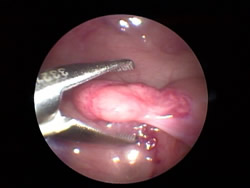

Eine Minikamera wird durch ein winziges Loch in den Bauch des Patienten eingeführt (Schlüssellochmethode)

Jetzt sind die Organe des Patienten deutlich auf dem Bildschirm zu sehen

Über einen weiteren kleinen Zugang wird dann die Operation mit Hilfe von speziellen Instrumenten durchgeführt